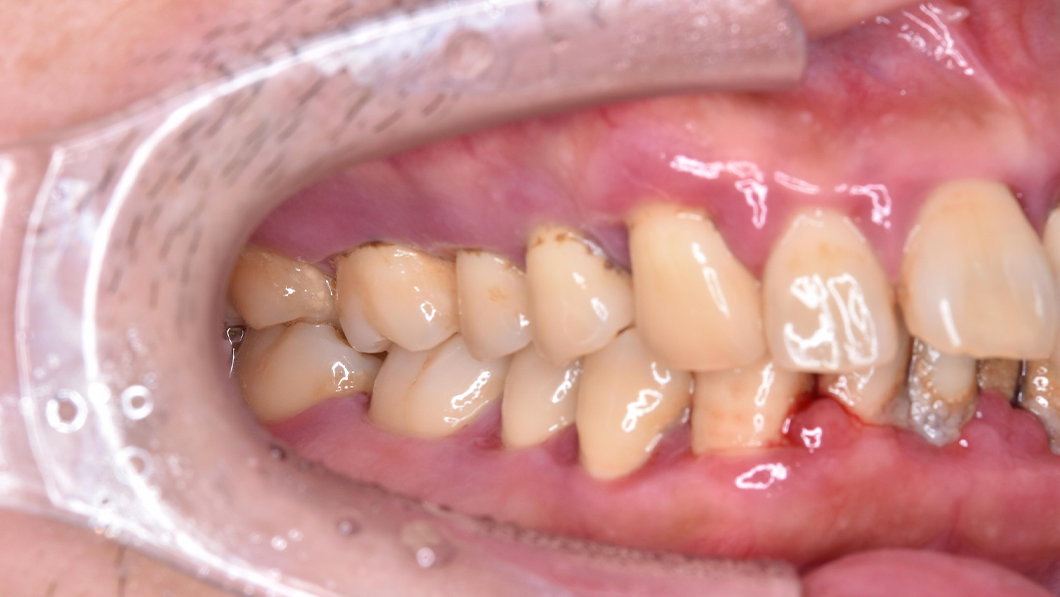

【40代 男性】歯周基本治療

治療後

主訴 全額的歯周病による歯周組織の炎症

治療内容 SC、SRP、歯科衛生士実地指導、TCH指導